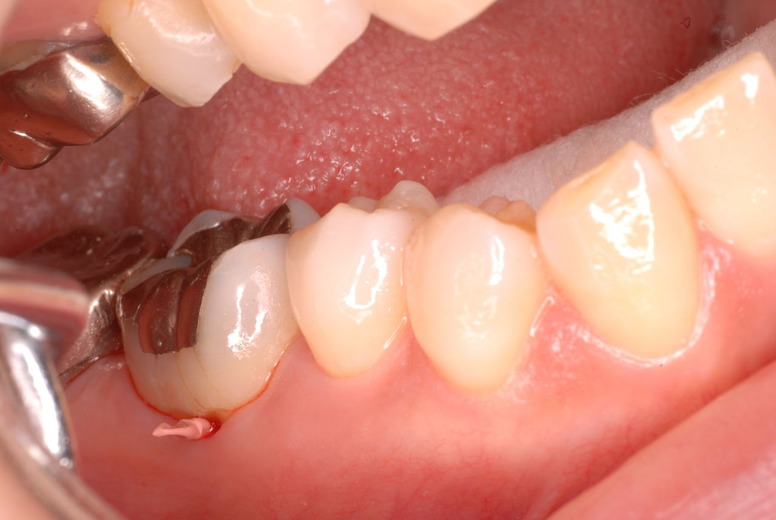

隣の14歳大臼歯がひどい虫歯になり治療不可能になりつつある状態のレントゲン